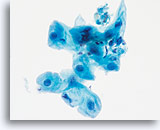

No diagnostic classification causes more debate than Atypical Squamous Cells (ASC). New terms rose from the revised classification of The Bethesda System (TBS) in 2001 and remain for TBS 2014. TBS indicates that the ASC category should be the diagnostic consideration when squamous abnormalities are present that are more marked than those attributable to reactive changes, but fall qualitatively or quantitatively short of the diagnostic criteria for a low grade or high grade squamous intraepithelial lesion. Furthermore, TBS stresses the importance of qualifying this diagnosis as “undetermined significance” (ASC-US) or “cannot exclude HSIL.” (ASC-H)

The proper classification of ASC challenges the cytotechnologist and pathologist and, writing any chapter describing the morphologic criteria of ASC is challenging, given the subjectivity of this interpretation. Since the adoption of TBS, laboratory professionals interpreting the conventional Pap smear may have used this category as a “catch all” for smears that are difficult to classify.

Artifacts inherent to the conventional Pap smear, such as air-dried or partially obscured cells, may result in an ASC diagnosis. The degree of apparent atypia in reactive cells may also be exaggerated by air-drying or smearing. These issues result in the artifacts that make it difficult for the cytotechnologist and pathologist to adequately visualize the nuclear detail of the cells in question, resulting in a less than definitive diagnosis.

The immediate wet fixation that is used in the ThinPrep process may allow the pathologist and cytotechnologist to move away from the ASC “catch all” and better differentiate between cellular changes due to reactive conditions, definitive squamous atypia, and dysplastic lesions. This is not to say that ASC interpretations are eliminated by the adoption of the ThinPrep Pap Test, but the laboratory staff has the opportunity to refine their morphologic criteria, eliminating certain “ASC” cases arising from poor preparation, and better identifying cases that may

harbor abnormality.

The ThinPrep Pap Test® minimizes the troublesome artifacts inherent in smear and spray fixation. This allows for

the nucleus to be adequately visualized facilitating a more definitive diagnosis. The epithelial cells that are generally incorporated in the ASC category are the mature squamous and squamous metaplastic cells exhibiting changes that are minimal and fall short of a diagnosis of LSIL or HSIL. The nuclei are slightly enlarged and this enlargement is compared to the normal entity of the same cell type. The nuclei may show slight nuclear membrane irregularities but are more often smooth. When dealing with the metaplastic component, one needs to make sure that the irregularities aren’t due to a vacuole(s) pushing the nucleus into the aberrant shape. The chromatin pattern is finely granular and evenly distributed. Chromocenters or nucleoli are generally inconspicuous or absent unless a reactive process is occurring in conjunction with the atypia at which point the differential diagnosis of reactive needs to be considered depending upon the presence or lack of the other criteria.

With either conventional or ThinPrep® slides, an ASC interpretation may arise from any of several different cellular changes, including but not limited to, squamous atypia, atypical squamous metaplasia, and atypical parakeratosis. The criteria for ASC on the ThinPrep Pap Test are as follows:

The images that follow are ThinPrep® Pap Test specimens that reasonably could be interpreted as reactive changes,

ASC-US, and LSIL.

As previously mentioned, ASC will not be eliminated by the adoption of the ThinPrep® Pap Test. In fact, the better cellular preservation that is afforded by liquid fixation can lead to over interpretation of nuclear size and chromatin as ASC if one is not familiar with the consequences of liquid fixation as discussed in the introductory material regarding “microscopic evaluation of ThinPrep slides”. There are circumstances where laboratory staff may transiently experience an increase in their use of ASC classification immediately after adoption of the ThinPrep Pap Test, then, after gaining experience, see that rate drop below that which was experienced with the conventional Pap.

ASC, as long as it remains a category in TBS, will be used by pathologists because of inherent subjectivity of human diagnosis, and variable interpretation of criteria. Also important is the biologic nature of Human Papilloma Virus (HPV) that causes morphologic perturbations in cells that are less than LSIL. The morphologic changes caused by HPV are discussed in greater detail in the section covering Low Grade Squamous Intraepithelial Lesions. The role of this virus in the causation of ASC has created the opportunity to determine the relative risk of ASC changes by the determination of high- vs. low-risk types of virus through ancillary testing of the material in the ThinPrep Pap Test vial.